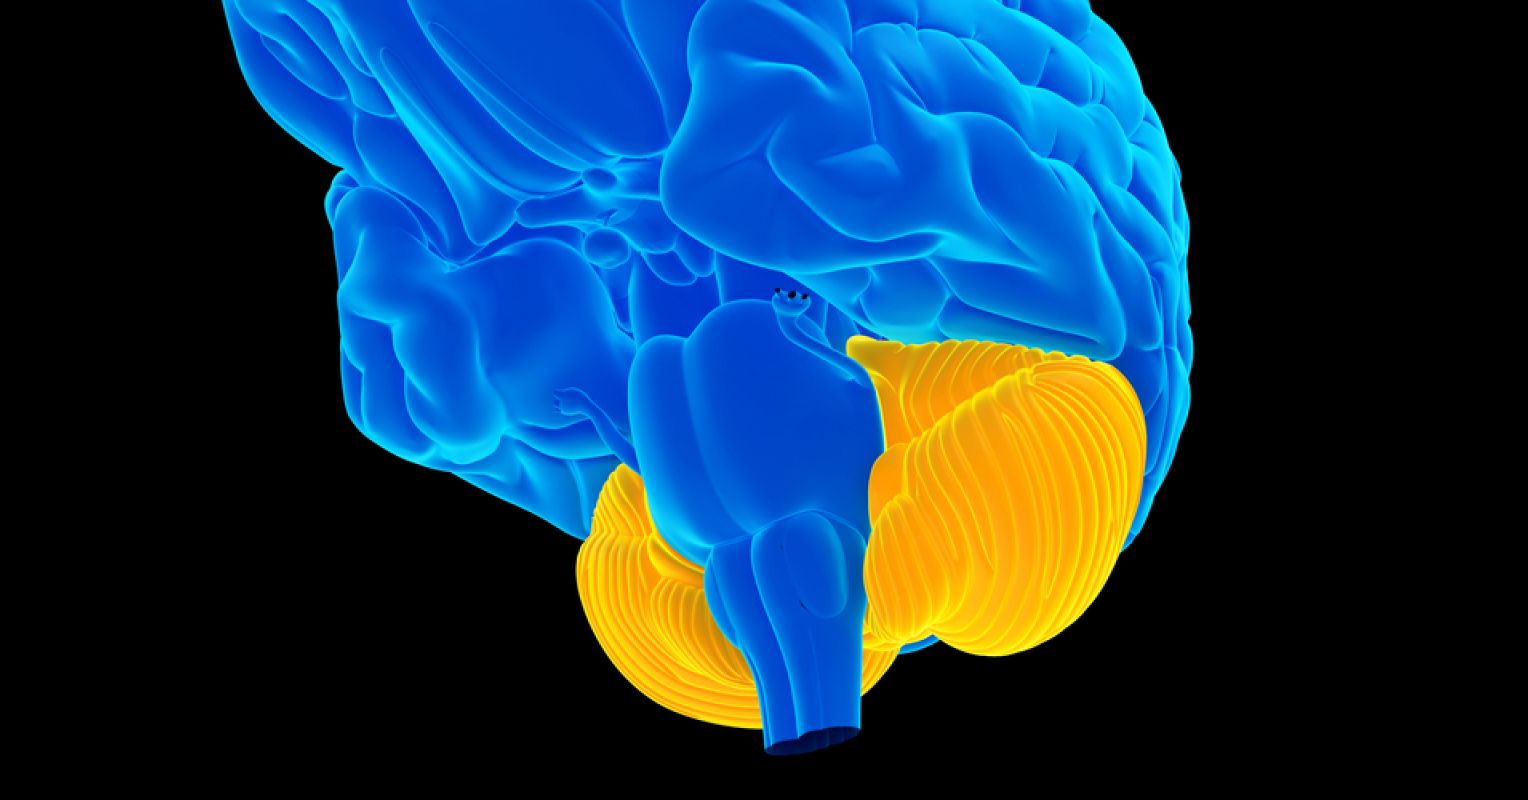

Cerebellum in orange. Cerebellar means “relating to the cerebellum.” It’s the sister word to cerebral, which means “relating to the cerebrum.”

Source: Sebastian Kaulitzki / Shutterstock